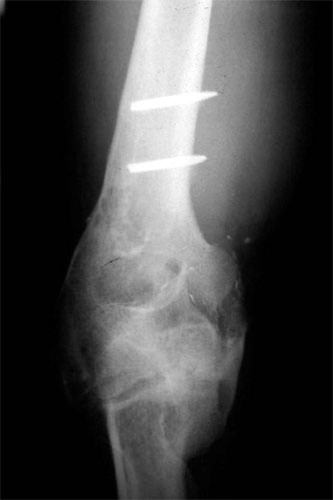

The pictures depict the application of the dynamic external fixator, which stabilized and provided early motion to the rigid elbow after aggressive release of the capsule and bone excision.

E.R. is a 26 year old male lifeguard who had a severe, unfortunate accident the first time he ever mounted a motorcycle. He was in a coma for many months with head trauma and had fractured his right elbow and forearm at the time of injury. He developed a condition called Heterotopic Ossification which meant that multiple joints “froze-up” due to deposits of calcium in the joint capsules. He was not able to walk until both hips were operated on by an internationally known hip surgeon who then referred him to Dr. Badia to address the stiff Right elbow and deformed forearm. In fact, at the initial visit, the patient stated that he had not moved the right elbow AT ALL for nearly 4 years and was unable to feed or groom himself with that hand. After a series of 3 operations to reconstruct both the elbow and forearm, this young man has gone back to swimming, work and a normal lifestyle.